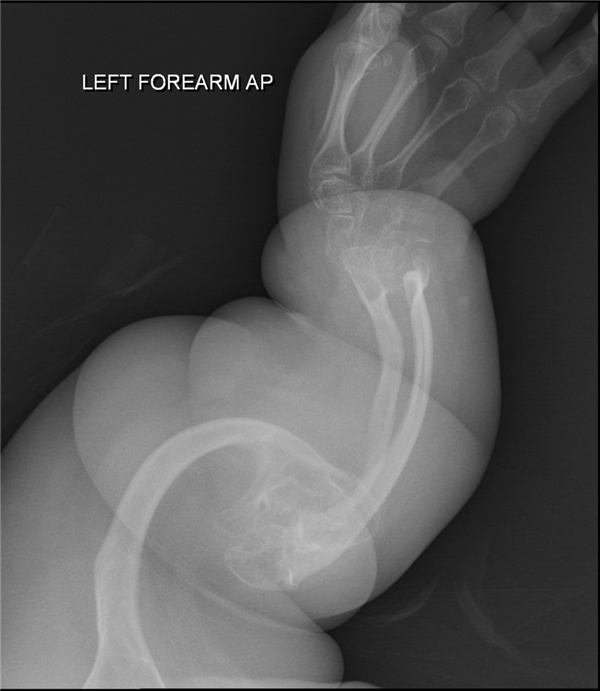

其他患者X光片——严重骨折

当时, 医生就给孩子拍摄了髋关节部位的X光片,结果在影像资料里发现了2处骨折,且处于不同的愈合阶段,说明2次骨折不是同一时间发生的。

接着医生又给孩子做了全身检查,在其他身体部位,又又又发现2处骨折,然后事态就升级了。

成骨不全症,也就是我们常说的瓷娃娃病,也称之为脆骨病,是一种罕见遗传疾病,发病率约为1/15000-1/20000。

典型特征就是骨头脆弱,微小的外力就能导致骨折,比如打个喷嚏、翻个身、伸手够东西,成年后骨折情况会相对少一些。